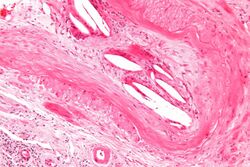

Micrograph showing a cholesterol embolus in a medium sized artery of the kidney. Kidney biopsy. H&E stain.

The microscopic examination of tissue (histology) gives the definitive diagnosis. The diagnostic histopathologic finding is intravascular cholesterol crystals, which are seen as cholesterol clefts in routinely processed tissue (embedded in paraffin wax).[7] The cholesterol crystals may be associated with macrophages, including giant cells, and eosinophils.[citation needed]